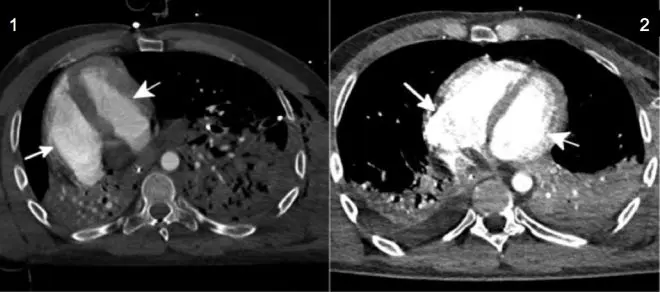

Un peu plus de 24 heures après que l'air ait été drainé hors de cet espace pleural, le cœur du patient s'est repositionné à gauche, de façon naturelle (clichés C et D).

Les échographies et les électrocardiogrammes de suivi n'ont pas montré de dysfonctionnement cardiaque à l'issue de cet épisode.